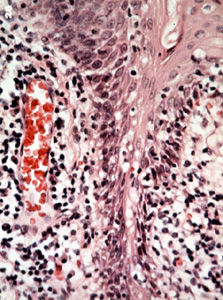

| Este

microfotografía muestra la

configuración de las papilas. Hay numerosos dedos, como proyecciones

cubiertas por epitelio escamoso respaldados por centros de conjuntivo

que contiene inflamación crónica.

| Note las

numerosas células inflamatorias en el tejido conjuntivo y los vasos

sanguíneos notablemente dilatados.

| A mayor poder

de resolución se observa la

reacción inflamatoria compuesta

por linfocitos y plasmocitos. Pero no se observa ninguna displasia en el

epitelio.